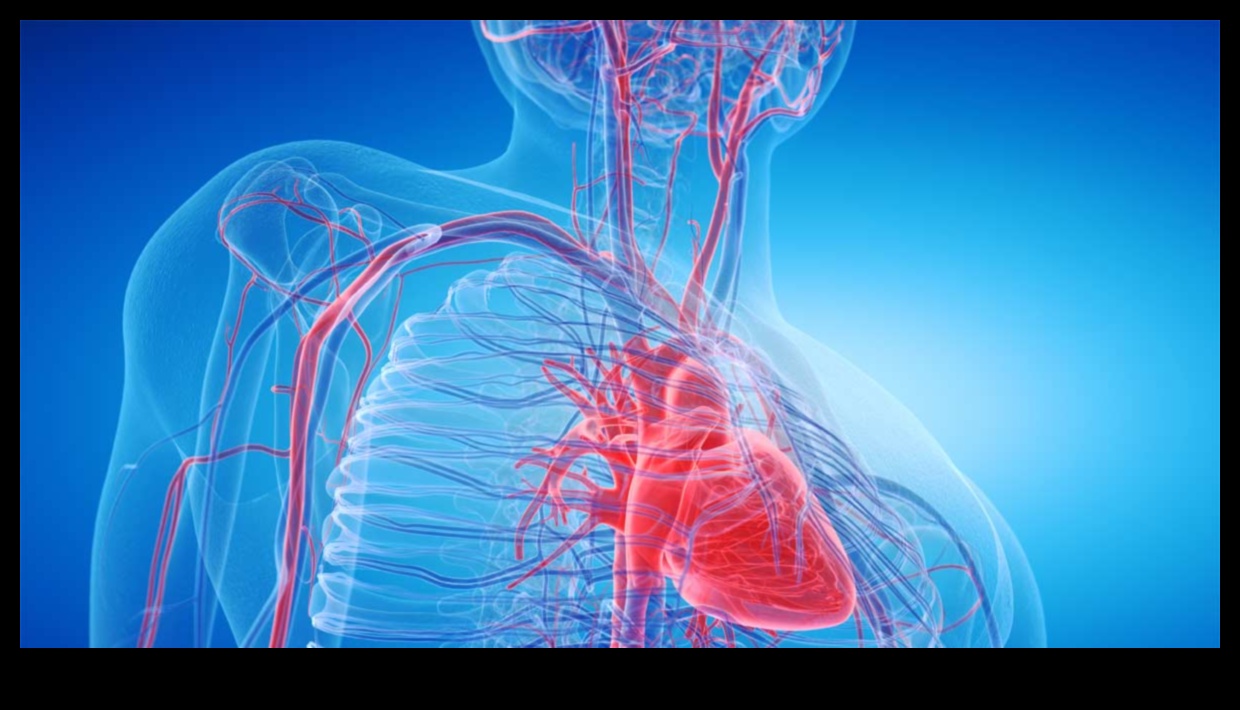

Ο συντονισμός του καρδιακού παλμού αυτό είναι ένα μέτρο της ελαστικότητας του καρδιακού μυός. Μετριέται με το χρόνο που πρέπει για οραθείτε να συσπαστεί τα έντερα και αργότερα οραθείτε να χαλαρώσει. Μια ωφέλιμος μέση έχει γρήγορο συντονισμό καρδιακών παλμών, ενώ μια μέση που δεν φαίνεται να είναι ωφέλιμος έχει πιο αργό συντονισμό.

Ο συντονισμός του καρδιακού παλμού συνδέεται λεπτομερώς με την καρδιαγγειακή φυσική στάση. Τα λαοί που μπορεί να είναι πιο καρδιαγγειακά έχουν γρηγορότερο συντονισμό καρδιακών παλμών μέσω τα λαοί που μπορεί να είναι πολύ λιγότερο fit. Είναι επειδή ένας ωφέλιμος καρδιακός μυς μπορούν συστέλλεται και οραθείτε να χαλαρώνει πιο απροσδόκητα μέσω μια μέση που δεν φαίνεται να είναι ωφέλιμος.

Ο συντονισμός καρδιακών παλμών θα οραθείτε να χρησιμοποιηθεί για τη διάσταση της καρδιαγγειακής ικανότητας και για τον εντοπισμό ανθρώπων που διατρέχουν κίνδυνο καρδιακής νόσου. Τα άτομα που έχουν αργό συντονισμό καρδιακού παλμού είναι μίλια πιο που μπορείς να σκεφτείς οραθείτε να αναπτύξουν καρδιακή νόσο μέσω τα άτομα που έχουν γρήγορο συντονισμό καρδιακών παλμών.

Ο συντονισμός του καρδιακού παλμού μπορείτε επιπλέον οραθείτε να χρησιμοποιηθεί για τη κάνοντας βελτιώσεις στη της καρδιαγγειακής υγείας. Η προπόνηση θα οραθείτε να βοηθήσει θυμίζει οικοδόμηση του συντονισμού του καρδιακού παλμού και στη κάνοντας βελτιώσεις στη της καρδιαγγειακής ικανότητας.

Συμπερασματικά, ο συντονισμός καρδιακών παλμών αυτό είναι ένα πολύτιμο λογισμικό για τη διάσταση της καρδιαγγειακής ικανότητας και τον εντοπισμό ανθρώπων που διατρέχουν κίνδυνο για καρδιακές ασθένειες. Η προπόνηση θα οραθείτε να βοηθήσει θυμίζει οικοδόμηση του συντονισμού του καρδιακού παλμού και στη κάνοντας βελτιώσεις στη της καρδιαγγειακής υγείας.

Η καρδιαγγειακή φυσική στάση είναι μίλια σημαντική για τη συνολική ευεξία και υγεία. Θα πρέπει οραθείτε να σας βοηθήσει οραθείτε να μειώσετε τον κίνδυνο καρδιακών παθήσεων, εγκεφαλικού επεισοδίου, διαβήτη τύπου 2 και ορισμένων ποικιλιών καρκίνου. Μπορείτε επιπλέον οραθείτε να βελτιώσει τη διάθεσή σας, οι βαθμοί ενέργειας και την υψηλή ποιότητα του ύπνου σας.

Η καρδιαγγειακή ταλέντο μετριέται με το VO2 max, που μπορεί να είναι η μέγιστη ποσό οξυγόνου που θα οραθείτε να χρησιμοποιήσει το πλαίσιο σας σε όλη τη διάρκεια της άσκησης. Όσο υψηλότερη είναι μίλια η μέγιστη VO2 σας, τόσο πιο καλή καρδιαγγειακή ταλέντο είστε.